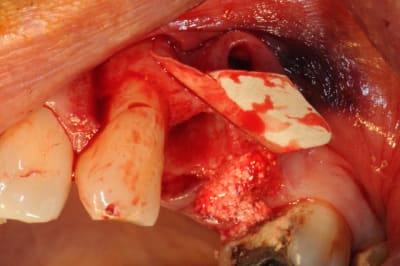

tiens voici des photos de ce matin...

patient avec kyste +++ aux apex et fenestration

je n'implante pas

je comble au Graftec

je met une membrane

je referme

8 mois après,

je vais implanter

comme je suis curieux, j'ouvre large et je regarde;

c'est décevant,le volume est là mais l'os n'est pas génial.

voilà pour les photos...

pendant que je forais, et le patient le sentait également, je sentais et entendais les particules de graftec.

en plus au bout de 8 mois j'aurai espéré trouver quelque chose de mieux non ?